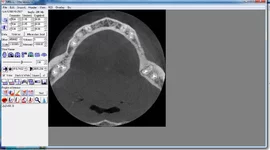

Вот так выглядит КТ другого типа

_02.webp

Это три проекции, которые просмотрщик показывает синхронизируя между собой.